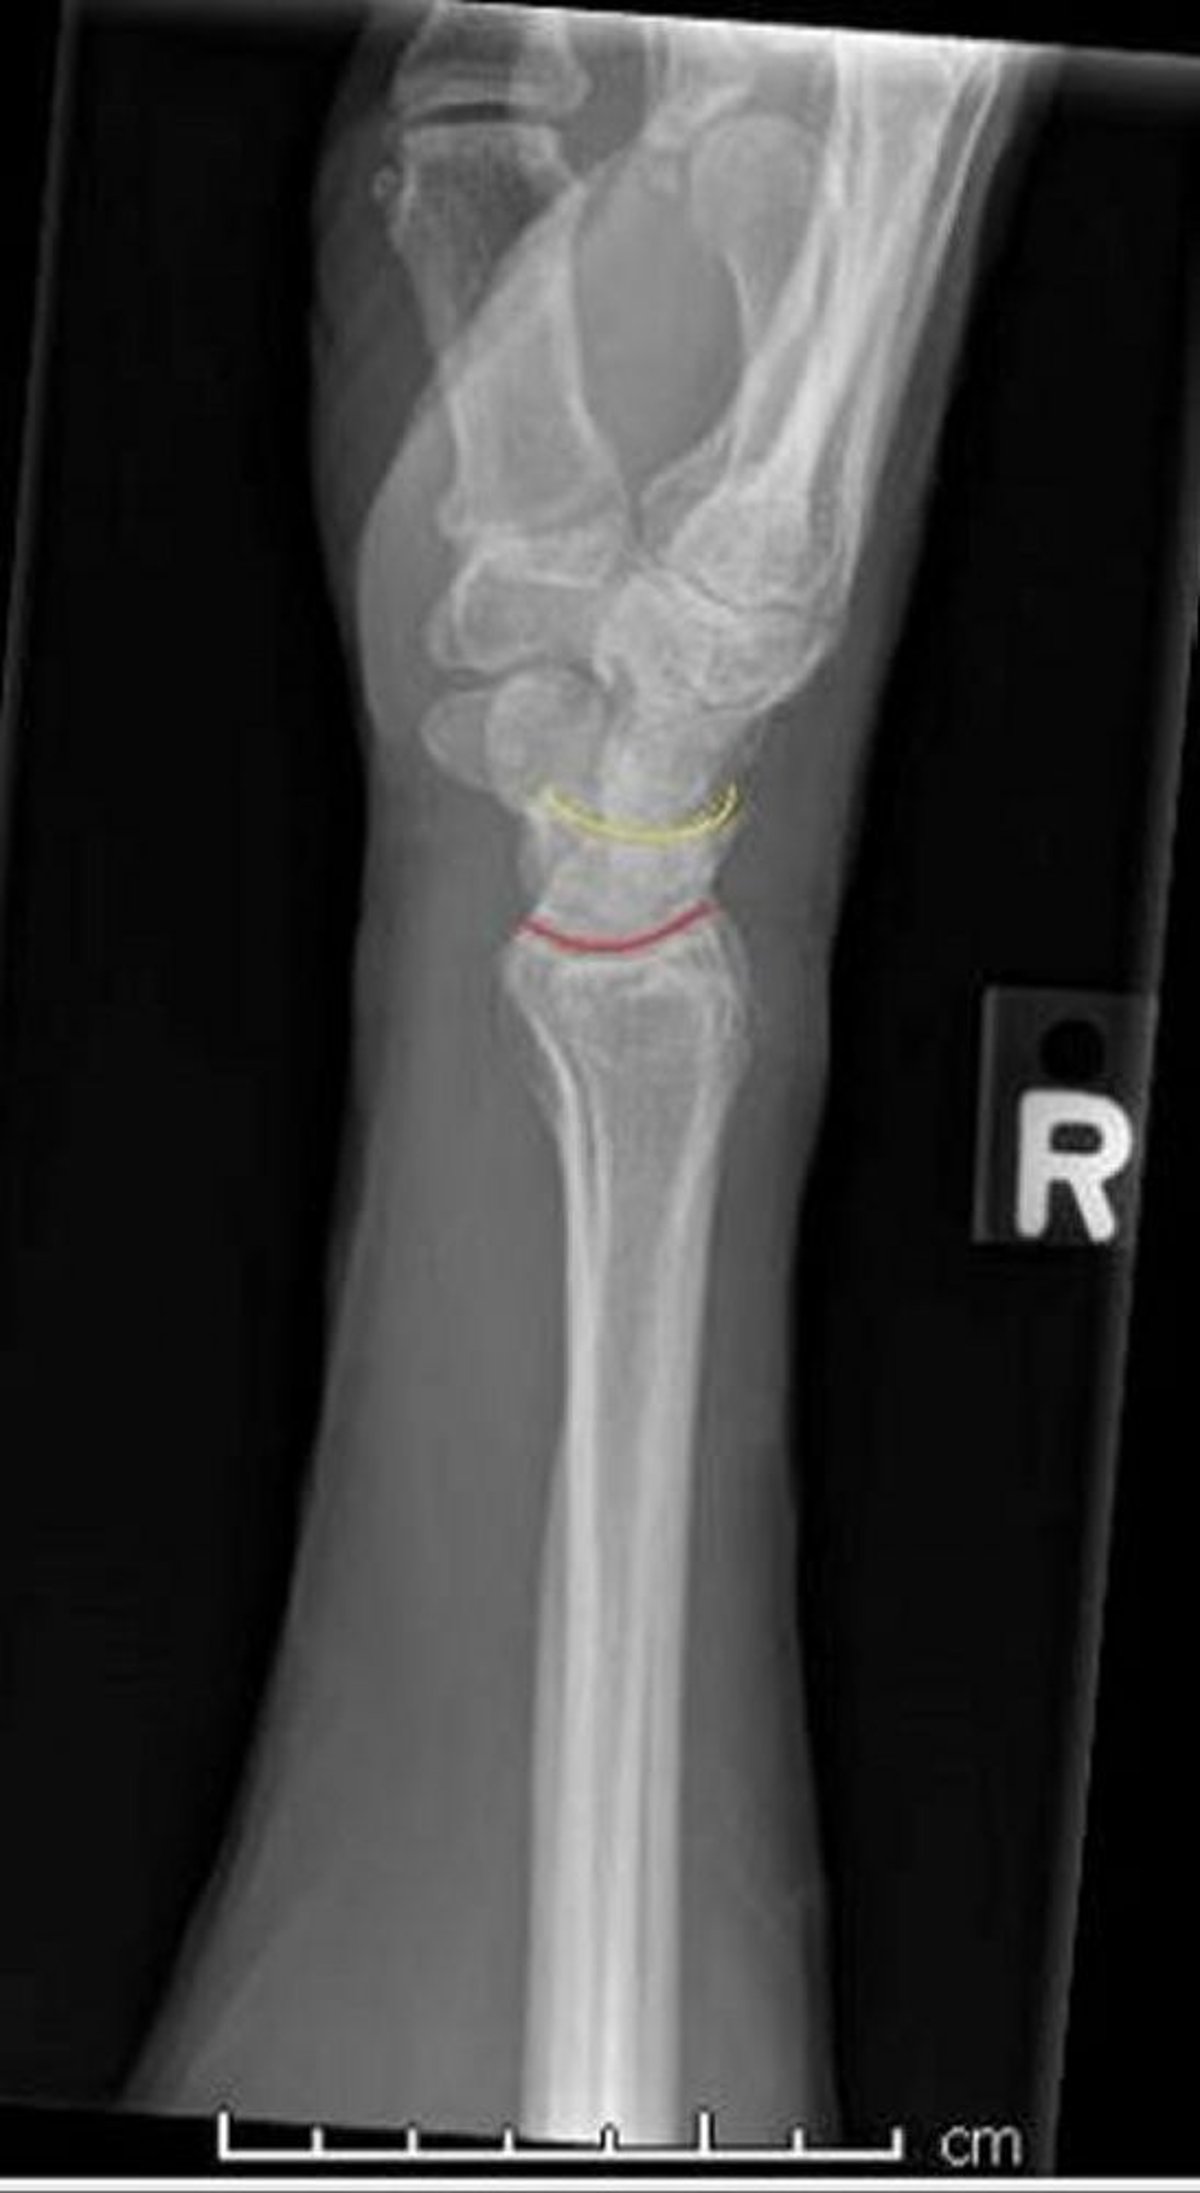

Poignet normal: vue latérale

Cette vue de profil d'un poignet normal montre l'interface normale entre le radius et le semi-lunaire (ligne rouge) et le semi-lunaire et le capitatum (ligne jaune).

Image courtoisie de Danielle Campagne, MD.